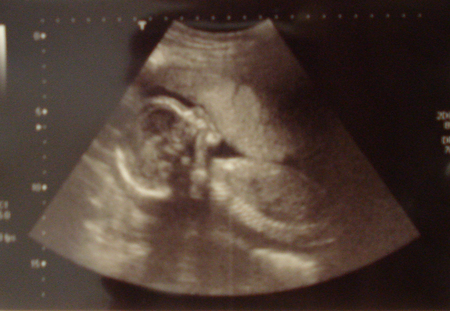

Экватор, отчетыА я вот сегодня сонная встала с утра, посмотрелась в зеркало и поняла, что полностью пропустила свой экватор! Вот мамаша. Взяла фотик и исправилась.

Вдобавок, нам по УЗИ на недельку больше. Вот такие вот мы